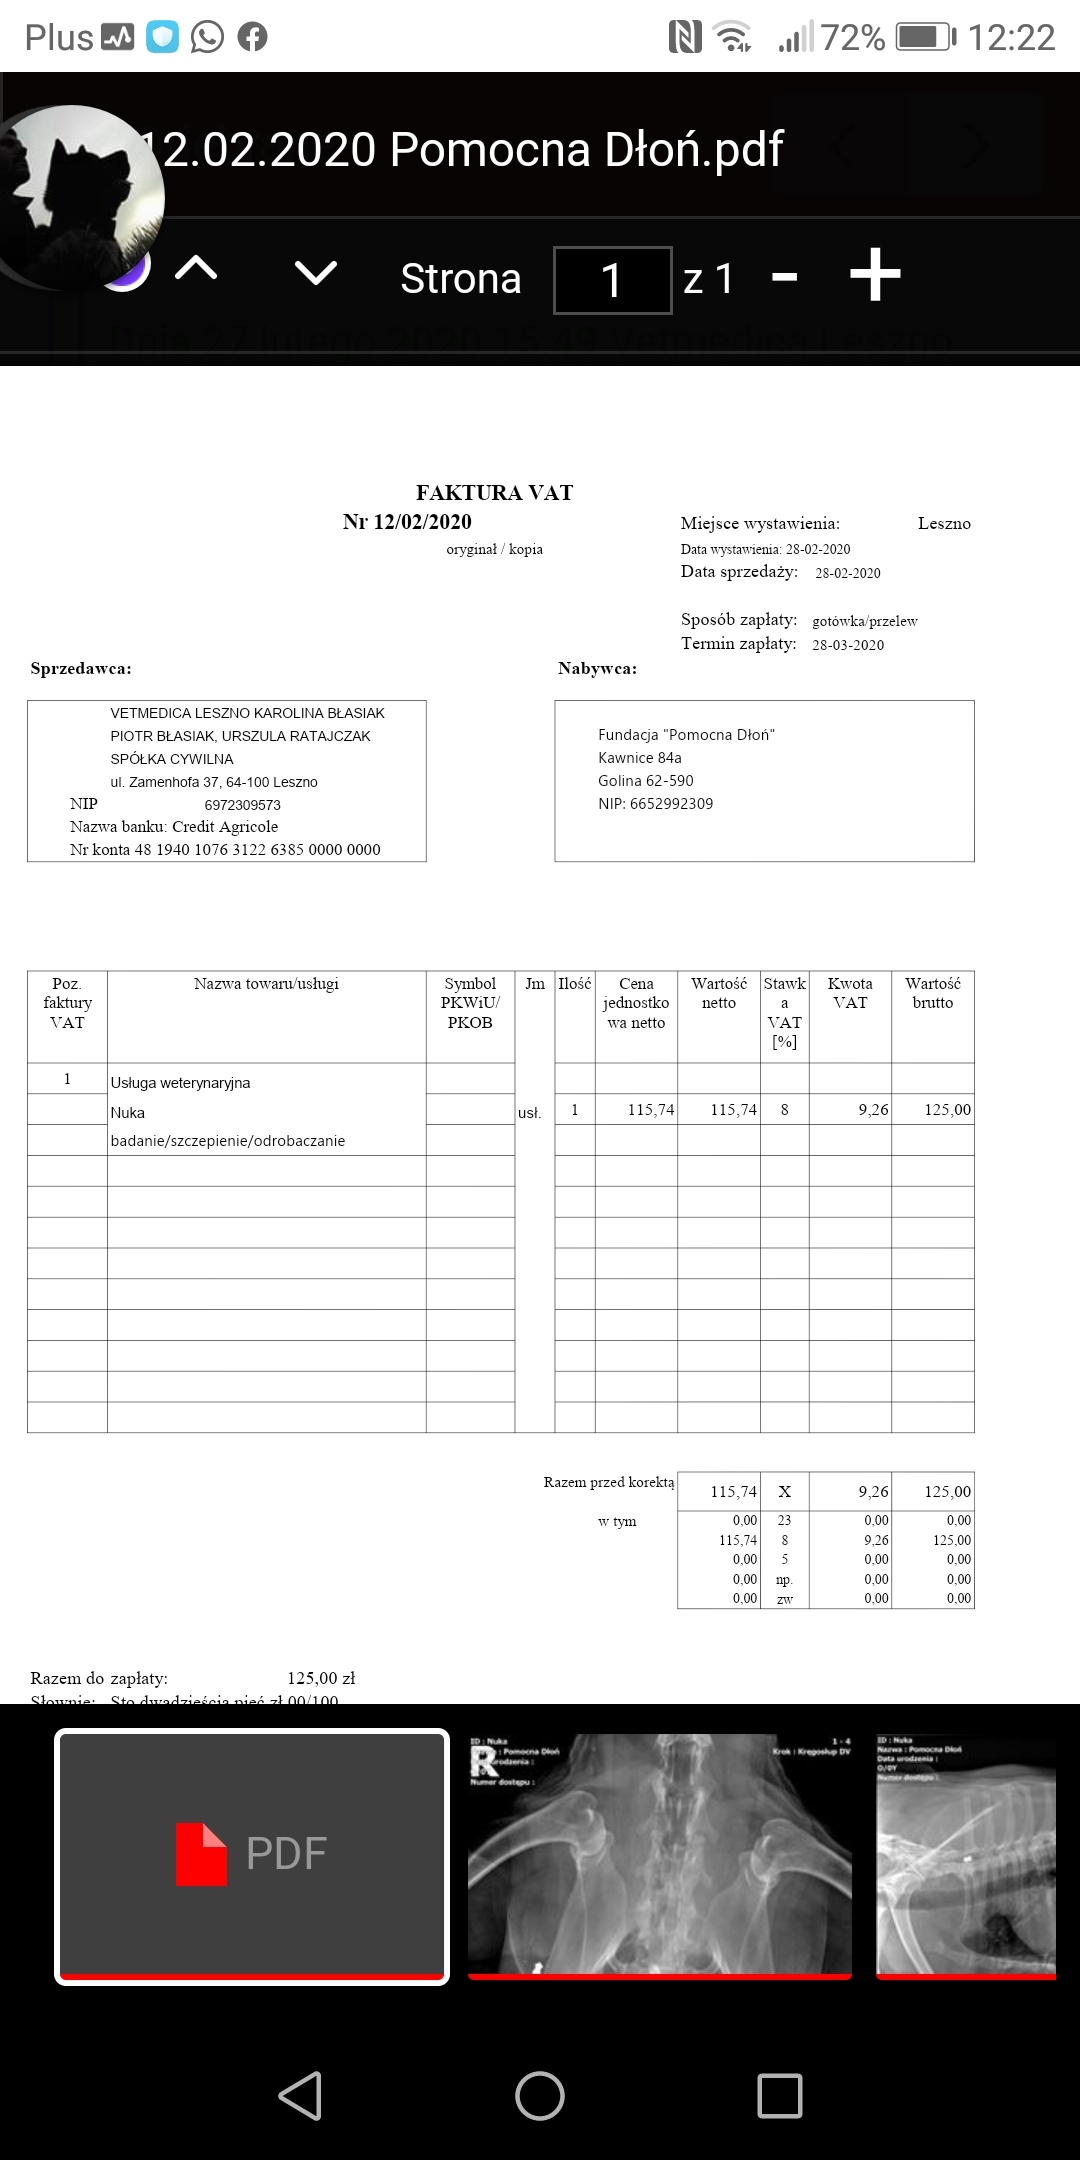

NA zdj fakturka jeszcze za badania i szczepienie